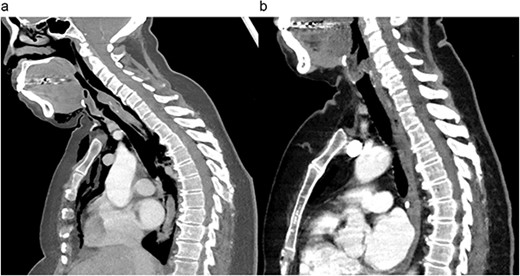

Preoperative (a) and postoperative (b) sagittal CT views of the thoracic cavity, demonstrating a large posterior tracheal defect extending to just above the carina, and its resolution postoperatively.